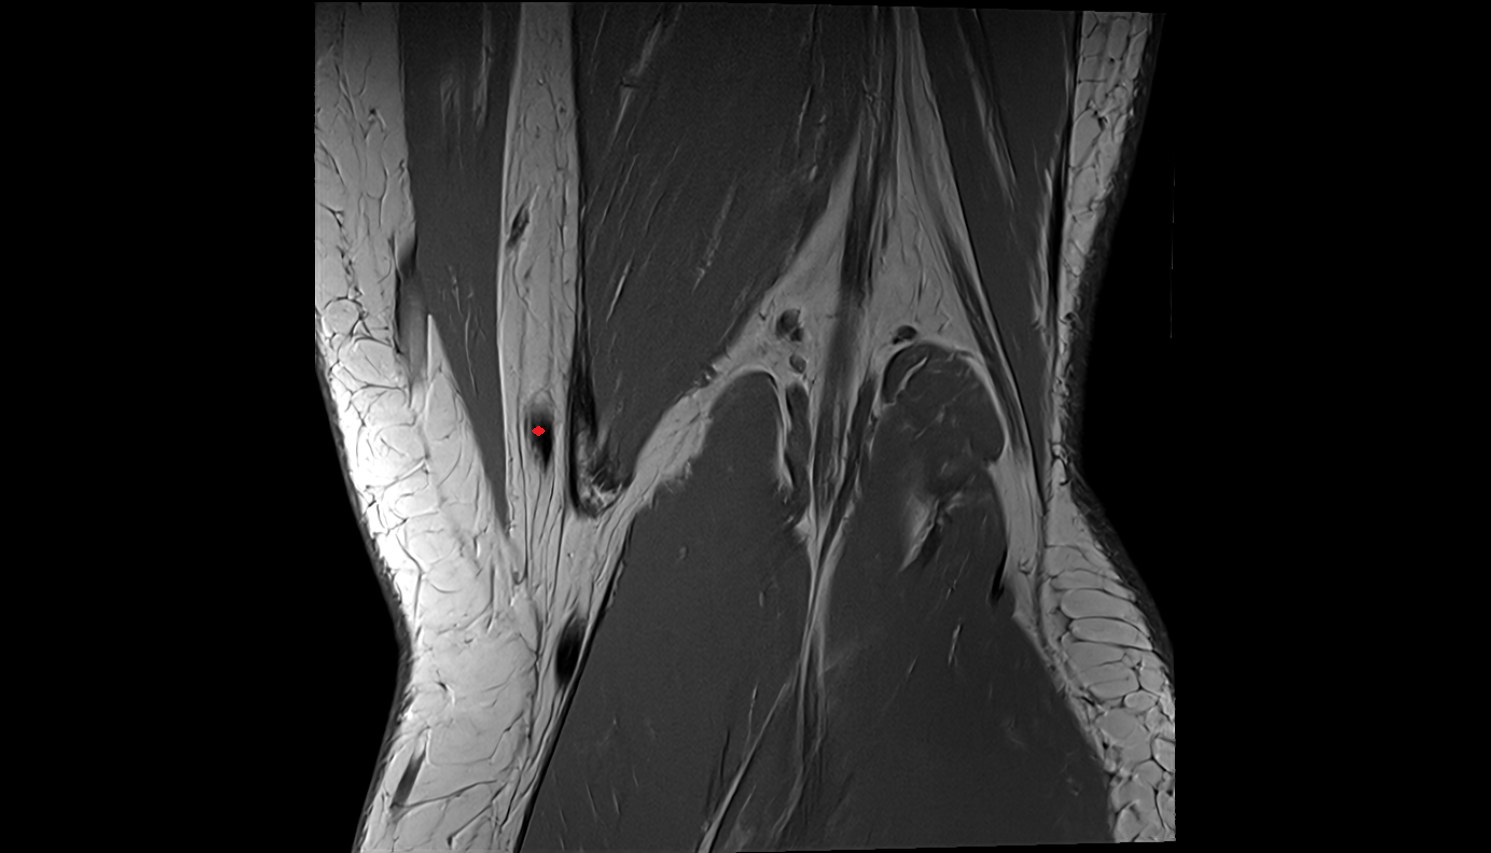

- Knee Joint